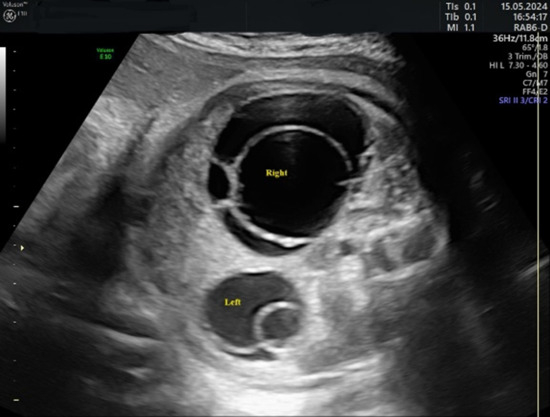

In 75% of the cases diagnosed, the cyst had the appearance of a simple cyst. Ultrasound revealed a unilocular, echoless cyst that was well circumscribed, had thin walls, and in some cases had multiple intracystic septa. The “daughter cyst sign” was present in four cases (33%) in the form of a small, round, anechoic structure within the cyst (Figure 3).

Figure 3.

Ultrasound axial view. Simple ovarian cysts in the 33rd week of pregnancy. Smaller cysts (arrows) are daughter cysts that are present on both sides.